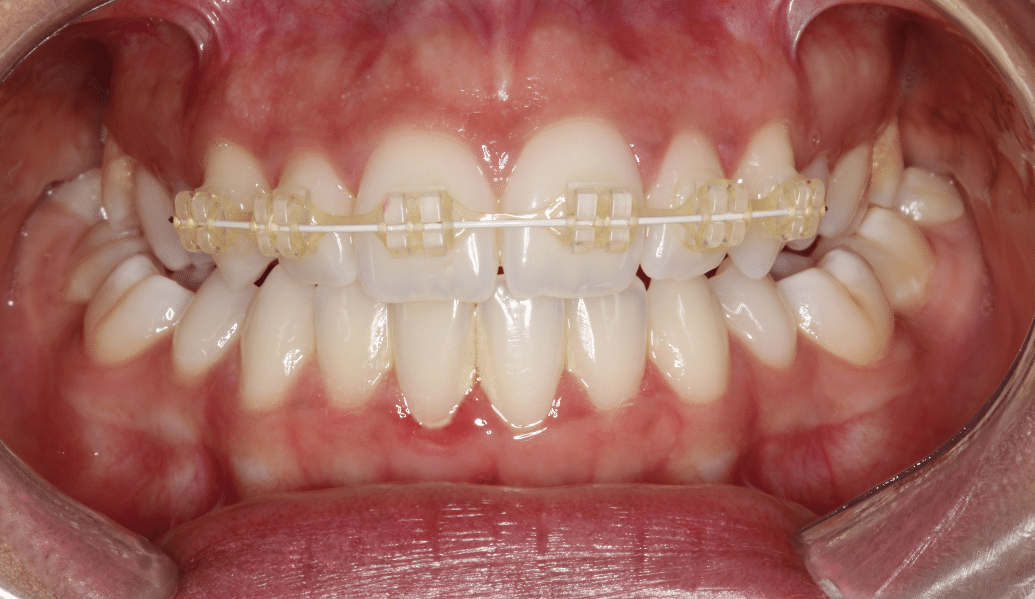

learn moreDental implants and us – together we can recreate a naturally beautiful smile.